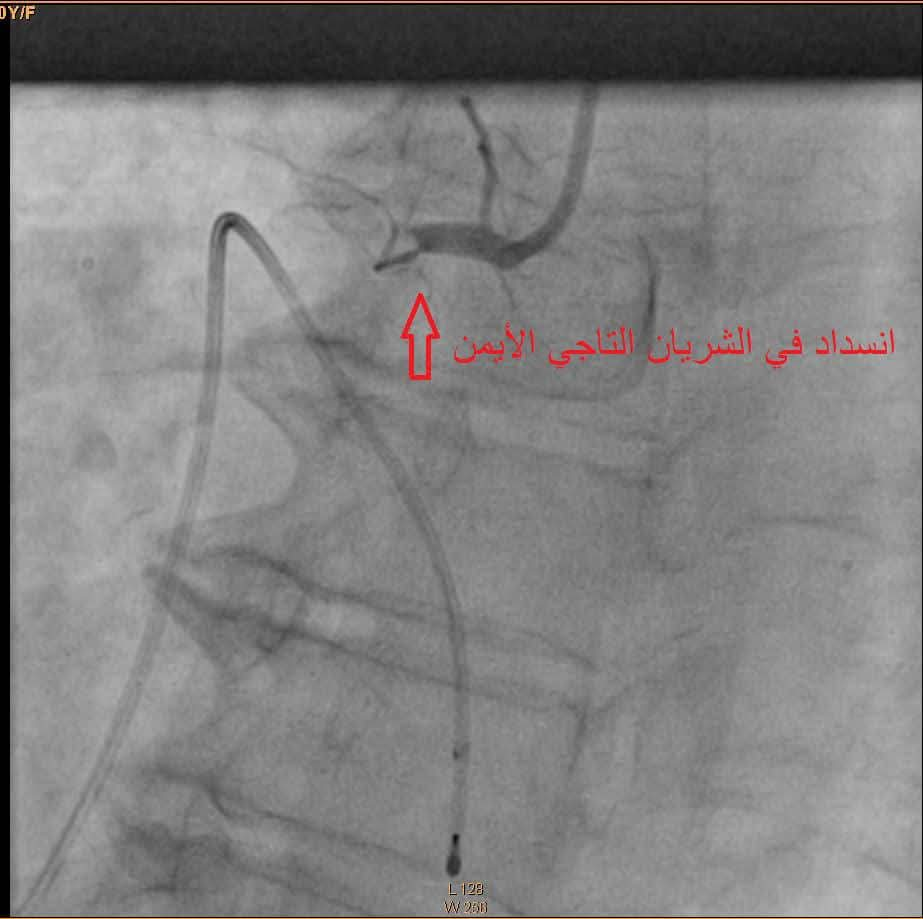

وبحسب استشاري القلب الدكتور محمد الهزيم، فقد تم تشخيص الحالة باحتشاء حاد في عضلة القلب السفلية مصحوب بصدمة قلبية واضطراب كامل في التوصيل الكهربائي للقلب، وهو ما استدعى تدخلاً إسعافياً عاجلاً.

جرى نقل المريضة مباشرة إلى وحدة البرج للقسطرة القلبية، حيث خضعت لعملية عاجلة تضمنت تركيب جهاز منظم لضربات القلب وفتح الشريان التاجي الأيمن مع وضع دعامة دوائية ناجحة. وقد شهدت حالتها تحسناً سريعاً بعد العملية.